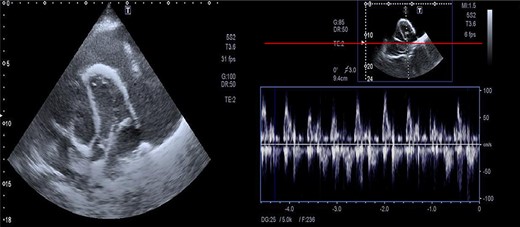

Massive precardial effusion with a swimming heart (A); respiratory variability at the mitral inflow level (B).

All patients with heart failure should have an echocardiogram, which gives a valuable opportunity to check for constrictive pericarditis. The echocardiography’s diagnostic criteria for constrictive pericarditis are the ventricular septal shift, medial mitral e’ ≥ 9 cm/s, and hepatic vein expiratory diastolic reversal ratio of ≥0.79 [8]. Echocardiography of our case showed enlarged precordium, massive pericardial effusion, septal bounce and respiratory variability in mitral and tricuspid inflow.